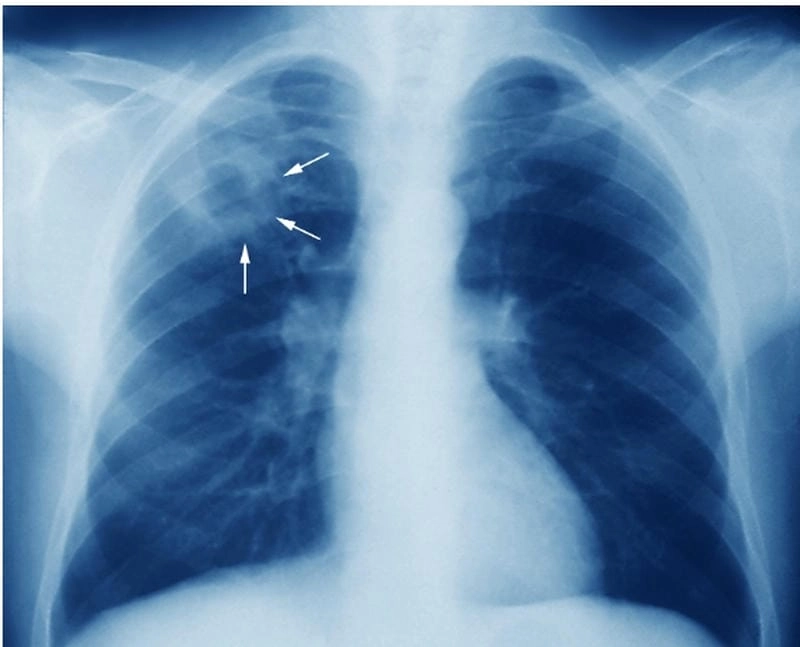

Bạn sẽ phải rùng mình khi chiêm ngưỡng hình ảnh bệnh lao phổi là như thế nào dưới ống kính y học thực tế. Những bức ảnh chụp X-quang cho thấy phổi bị tổn thương nặng, xuất hiện những đốm trắng mờ như bóng ma ám ảnh. Không chỉ là các tổn thương vật lý, đây còn là những “chứng tích sống” của căn bệnh âm thầm hủy hoại cơ thể qua từng hơi thở. Từ viêm nhẹ đến tổn thương lan rộng, hình ảnh bệnh lao phổi khiến người xem không thể rời mắt vì mức độ nghiêm trọng mà nó thể hiện rõ ràng qua từng chi tiết.

Cảnh báo: tổng hợp ảnh bệnh lao phổi chân thực này không dành cho người yếu tim. Đây là loạt hình ảnh y khoa được các chuyên gia sưu tầm và xác thực, ghi lại quá trình tiến triển của bệnh từ giai đoạn đầu đến giai đoạn nguy kịch. Từng mảng mô phổi bị ăn mòn, xơ hóa, hoại tử được phơi bày rõ nét dưới ánh sáng X-quang lạnh lùng. Những hình ảnh này không chỉ mang tính chất minh họa y học, mà còn là hồi chuông cảnh tỉnh cho bất kỳ ai còn lơ là với căn bệnh nguy hiểm này.